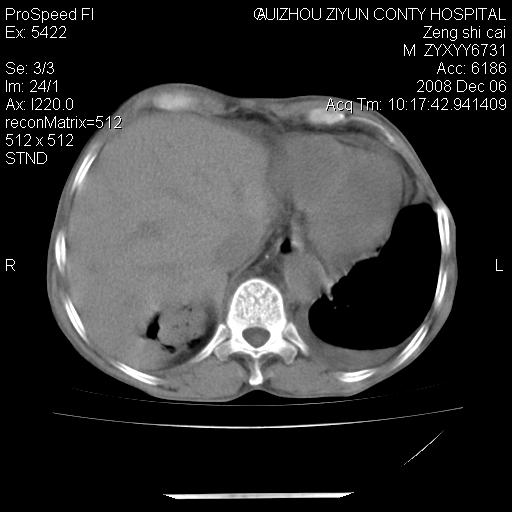

升结肠癌伴腹膜后淋巴结转移

右肺癌并纵隔淋巴转移,腹膜后转移可能性大,两侧胸腔积液